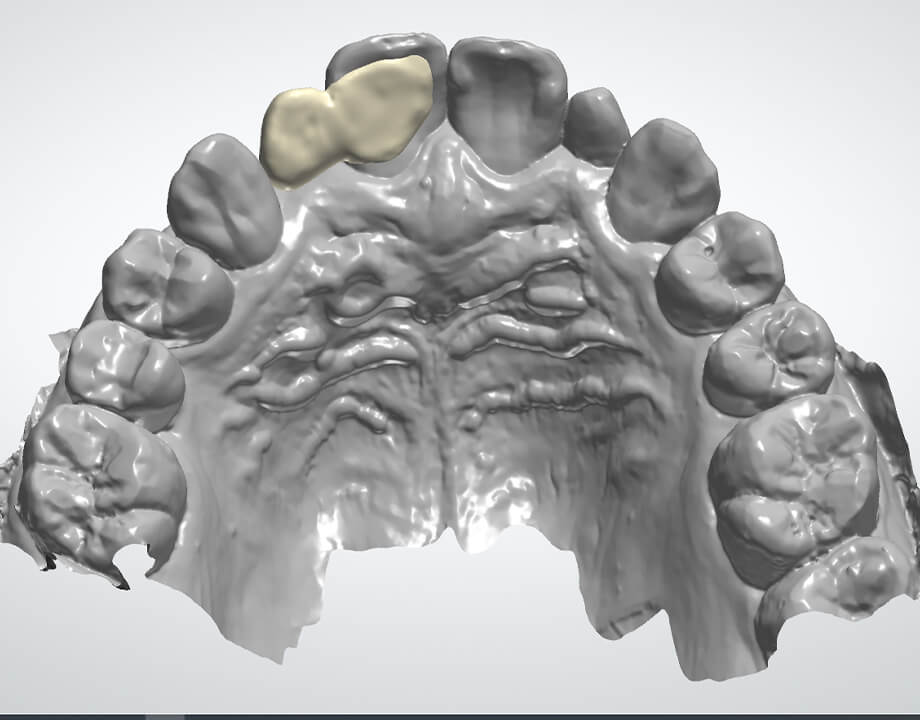

Case 01天然歯

ジルコニアレイアリング